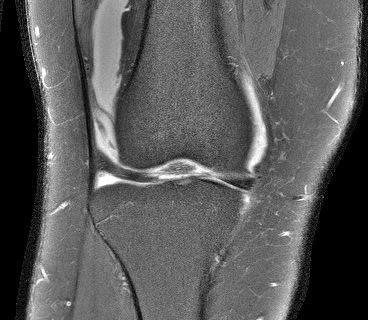

- •

To illustrate the low-rank characteristics of the matrix as described in Sec. III-A, Fig. 2 plots the singular values of for all three datasets. In each case, the matrix was calculated using the central 2424 k-space samples from the Nyquist grid and assuming a rectangular FIR filter support (i.e., ). As expected, all three matrices are approximately low-rank with a substantial approximate nullspace.